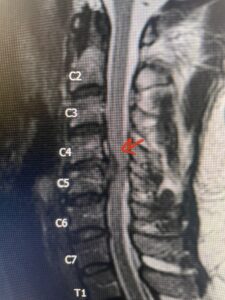

Fig 2a Sagittal and axial T2 weighted cervical MRIs demonstrating large C4 5 herniated disc with spinal cord compression red arrows

This 47-year-old male who four months prior was lifting weights developed sharp pain in his neck. After that he developed progressive numbness in his arms, neck pain and headache. He said that the right arm was worse than the left. On examination the patient had long tract weakness on the right side which included his triceps, finger extensors, hip flexors, and dorsiflexors. The patient did not have hyperreflexia. MRI (Fig. 2) demonstrated a massive, extruded disc herniation with severe cord compression. The patient because of progressive myelopathy and spinal cord compression was indicated for anterior cervical discectomy and fusion at C4-5 (Fig. 3). Patient had significant improvement of weakness and numbness post operatively.

Fig. 2a Sagittal T2-weighted cervical MRI demonstrating large C4-5 herniated disc with spinal cord compression (red arrow)